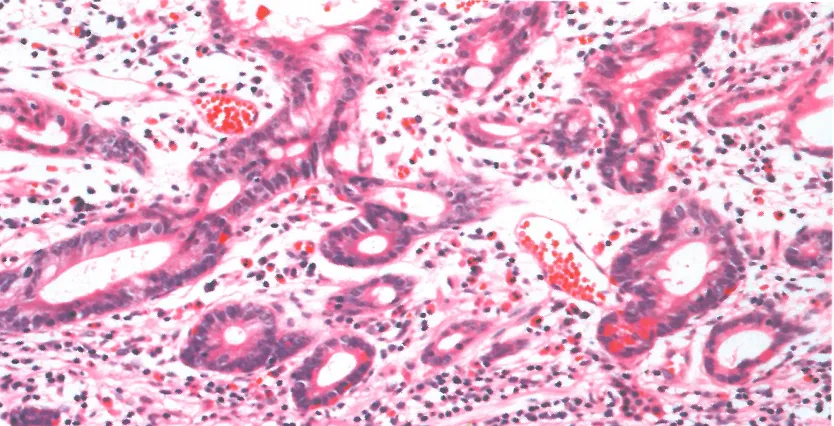

肠型高级别异型增生:肠型分化高柱状细胞核排列紊乱

胃型高级别异型增生:高柱状细胞核排列紊乱。

p53过表达